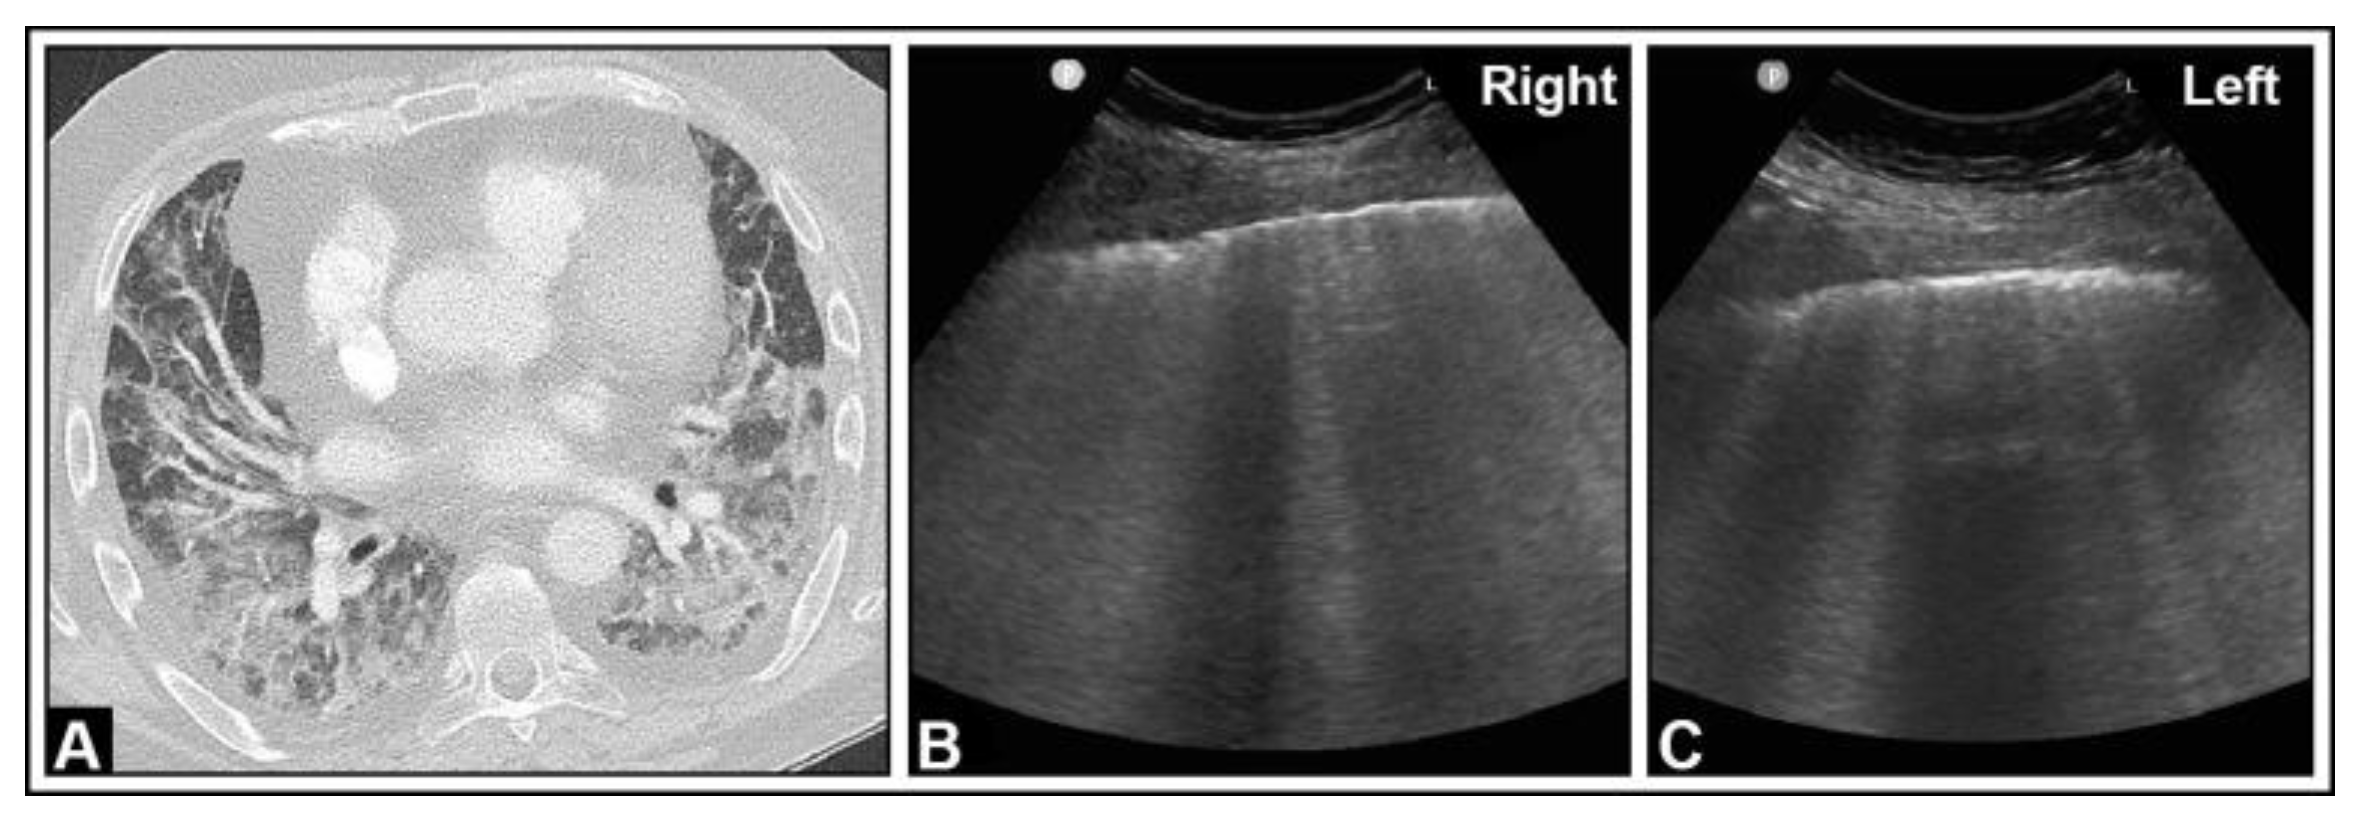

4. Pulmonary Edema and Acute Respiratory Distress Syndrome